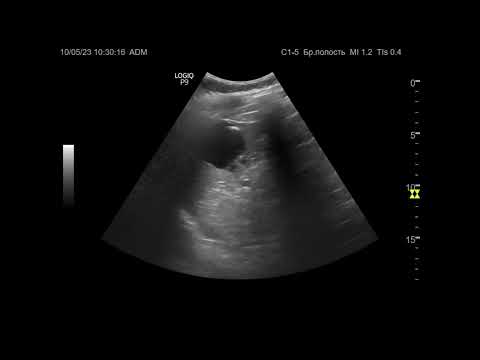

УЗИ. Доктор Иогансен. Выпуск 20. Эхинококковые поражения печени. Часть 2.

Вторая часть изложения темы "Эхинококковые поражения печени". Представлены ультразвуковые признаки эхинококковых кист печени и их классификации. Ссылка на Дзен: Ссылка на RuTube: